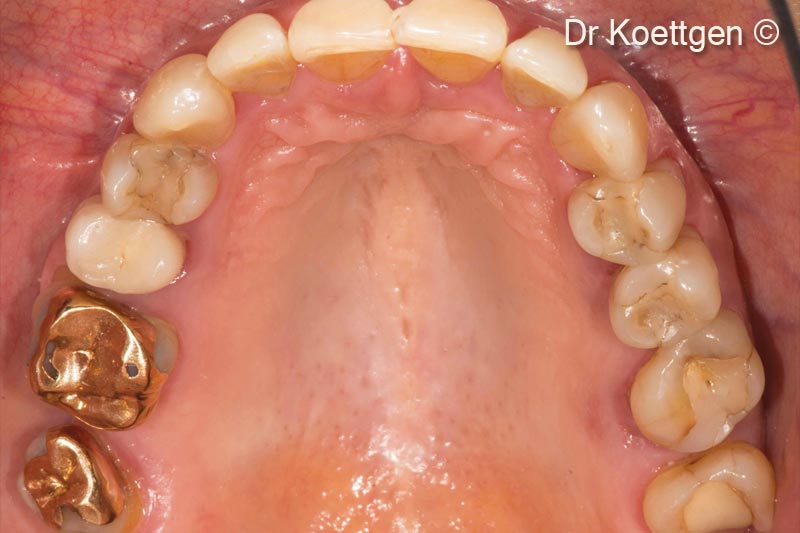

1. Initial situation